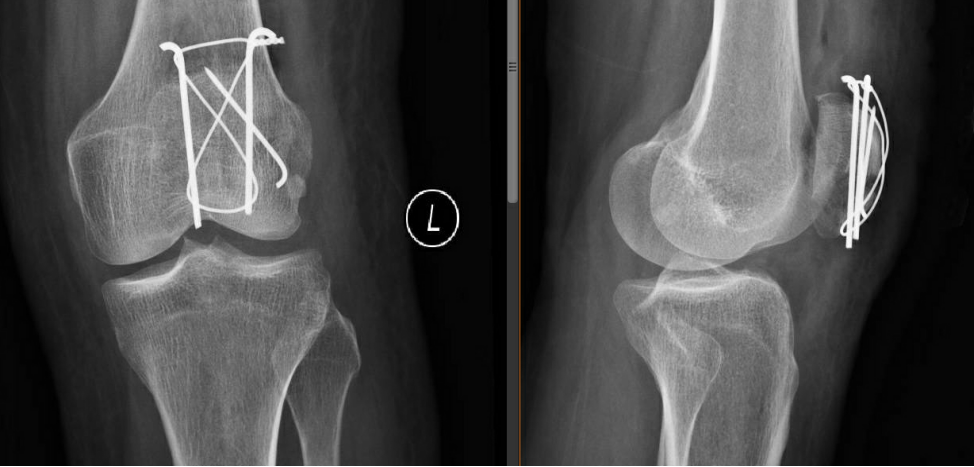

術(shù)后第二天復(fù)查左髕骨X線提示:左髕骨骨折術(shù)后改變,可見(jiàn)金屬內(nèi)固定器影,斷端對(duì)位對(duì)線佳,骨小梁尚規(guī)則,左膝關(guān)節(jié)在位,關(guān)節(jié)間隙尚可。